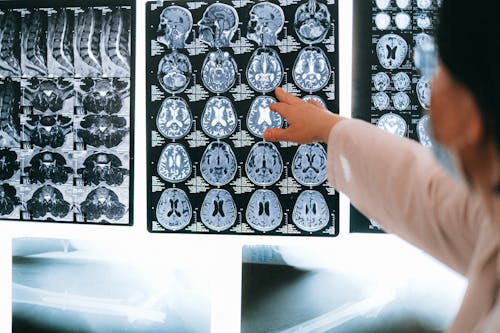

"내 이름이 뭐지? 어제 무슨 일이 있었지?" 영화나 드라마에서 자주 등장하는 기억상실증 장면. 주인공이 사고를 당한 후 모든 기억을 잃거나, 과거의 트라우마로 인해 특정 기간만 잊어버리는 클리셰는 시청자들의 마음을 사로잡습니다. 하지만 실제 기억상실증은 영화처럼 극적이지 않을 수 있습니다. 오늘은 '기억상실증'에 대해 의학적 사실을 바탕으로 상세히 알아보고, 영화 속 클리셰와 현실의 차이점까지 파헤쳐보겠습니다.

기억상실증(Amnesia)은 뇌 손상, 심리적 충격, 질병 등으로 인해 기억을 저장하거나 회상하는 능력에 장애가 생긴 상태를 말합니다. 일반적인 건망증과 달리, 기억상실증 환자는 전체적 또는 부분적으로 과거 경험을 완전히 잊어버리거나 새로운 정보를 기억하지 못하는 특징이 있습니다.

원인과 증상: 왜 기억을 잃을까?